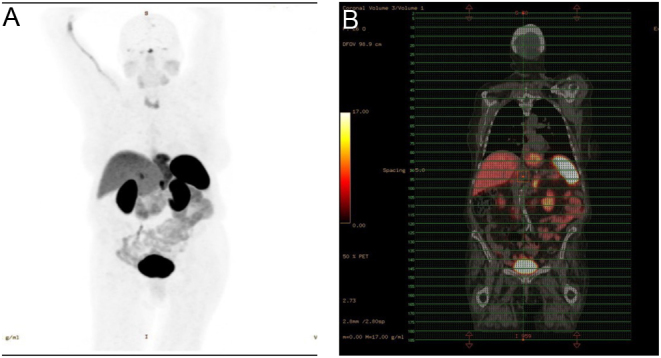

Summary: ACTH-secreting pituitary adenomas causing Cushing's disease (CD) typically present with weight gain, whereas weight loss and hypokalemia in endogenous Cushing's patients are suggestive of ectopic ACTH production. We report a case of CD presenting with atypical features of marked weight loss and hypokalemia. A 75-year-old female was admitted to the hospital with a history of profound weight loss, associated with uncontrolled hypertension, hyperglycemia, severe proximal muscle weakness, and hypokalemia. Subsequent investigations, including 24-h urinary free cortisol, 48-h low-dose dexamethasone suppression test, MRI of the sella, and bilateral inferior petrosal sinus sampling, confirmed CD without any evidence of ectopic ACTH production. She became eucortisolemic with medical therapy of ketoconazole and cabergoline, subsequently regained her weight, and became normokalemic. This case illustrates that patients with CD may present with symptoms and biochemical findings that would otherwise suggest ectopic ACTH production.

Learning points: Patients with CD do not always present with classical clinical features and may present with symptoms and biochemical findings that would otherwise suggest ectopic ACTH production. While most patients with CD typically lose weight after biochemical remission, some patients gain weight after the normalization of cortisol levels. This case highlights the need to entertain a broad differential in patients presenting with hypokalemia and weight loss and the need to exclude hypercortisolemia.